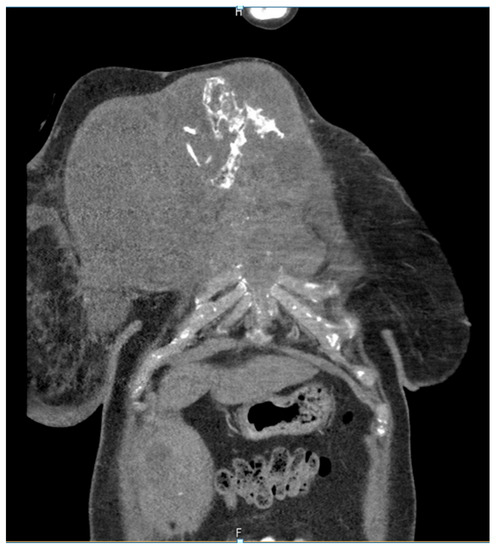

She returned to Bochum in June 2018 with the following symptoms: on the right ventral chest wall, she had a large tumor with a perforation in the pericardium of approximately 15 × 20 cm, an abdominal inguinal tumor on the right, and an ulcerating tumor on the lower left side of the abdomen. A computed tomography of the thorax and abdomen was performed in 09/2018 (Figure 2 and Figure 3) and a magnetic resonance imaging of the thorax was performed in 06/2018 (Figure 4 and Figure 5).

Figure 2.

Computed tomography of thorax and abdomen (CT Thx/Abd) in 2018. In this study, we detected a large tumor on the right anterior thorax with calcifications and invasion in the mediastinum.

Figure 3.

Computed tomography of the thorax and abdomen (CT Thx/Abd) in 2018. There is a large, partially calcified soft tissue structure of the right breast with central hypodensity and possibly mucinous parts. The image shows infiltration of the thoracic wall and transfer to the mediastinum, with destruction of the corpus and manubrium sterni and infiltration of the musculus pecotralis major and the musculus serratus anterior on the right. Additionally, destruction of the adjacent medial clavicle on the right and of the first rib medial on the right was observed. The formation directly infiltrates the mediastinum, with infiltration of the pericardium and direct contact with the aortic arch. The maximum extent of this conglomerate was 25.2 × 14.8 × 10.0 cm (VU 22.7 × 16.6 cm axial; not fully recorded cranially). There was no flow obstruction of the right-side vessels of the upper thoracic aperture.